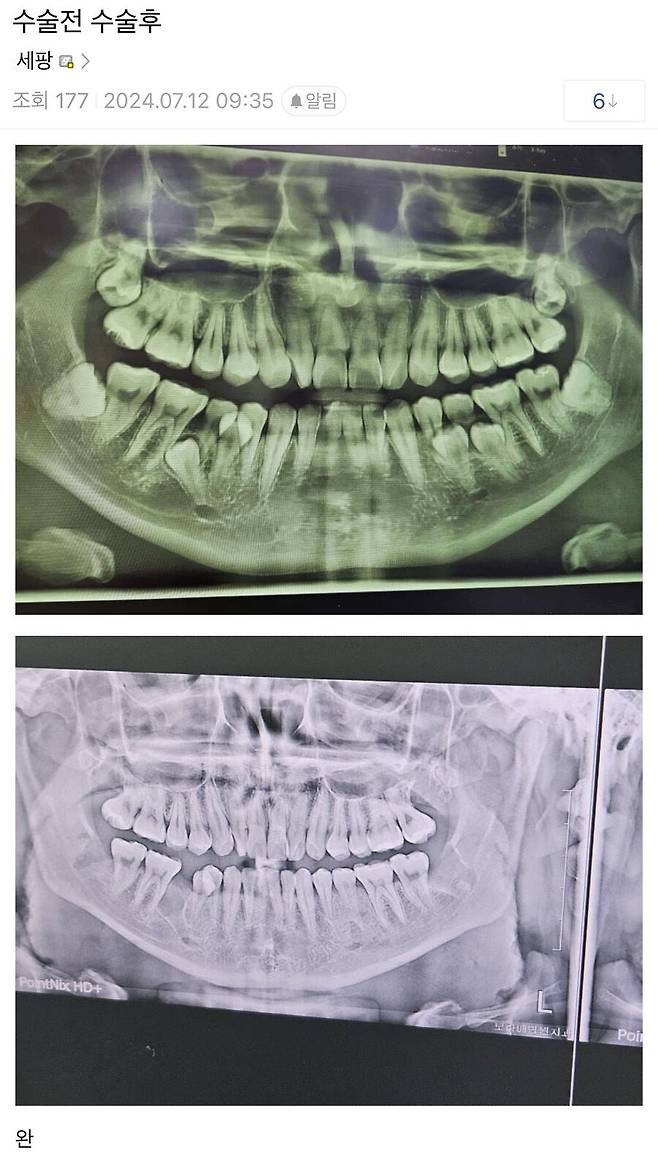

역대급 사랑니 수술 전, 후

으악... 왼쪽 아래 치아..왜 저렇게 나요..